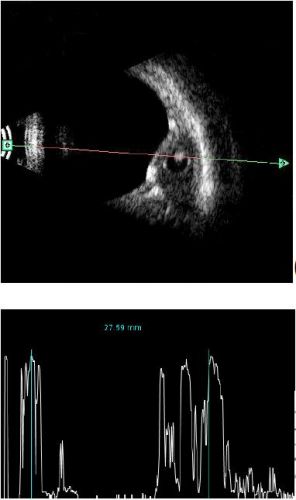

rectus muscle cystecercosis

rectus muscle cyst with internally two high reflective spot that is scolex ,,,with globe indentation by the cyst